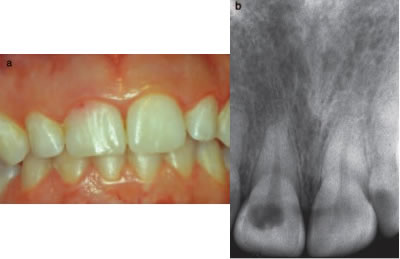

A major challenge with ECIR lesions is they are typically asymptomatic and difficult to discover unless they are at a class III or IV. If clinically detectable, a tooth may take on a pinkish hue near the gingival margin, due to the highly vascular inflammatory tissue that is replacing the tooth structure. There may be a cavitation that is detectible with an explorer. The tooth structure is usually hard, not sticky as is the case when detecting a carious lesion, however large lesions may also have secondary decay as a result of the defect creating a hygiene issue. Localized periodontal inflammation may also be observed for this reason as well. (Figures 5 and 6)

Figure 5- Small ECIR defect detectible at the gingival margin of #8. The pinkish hue of the inflammatory tissue is visible through the translucent enamel. Associated radiograph is included.

Figure 6- localized periodontal inflammation as a result of an ECIR lesion #9. Associated radiograph is included.